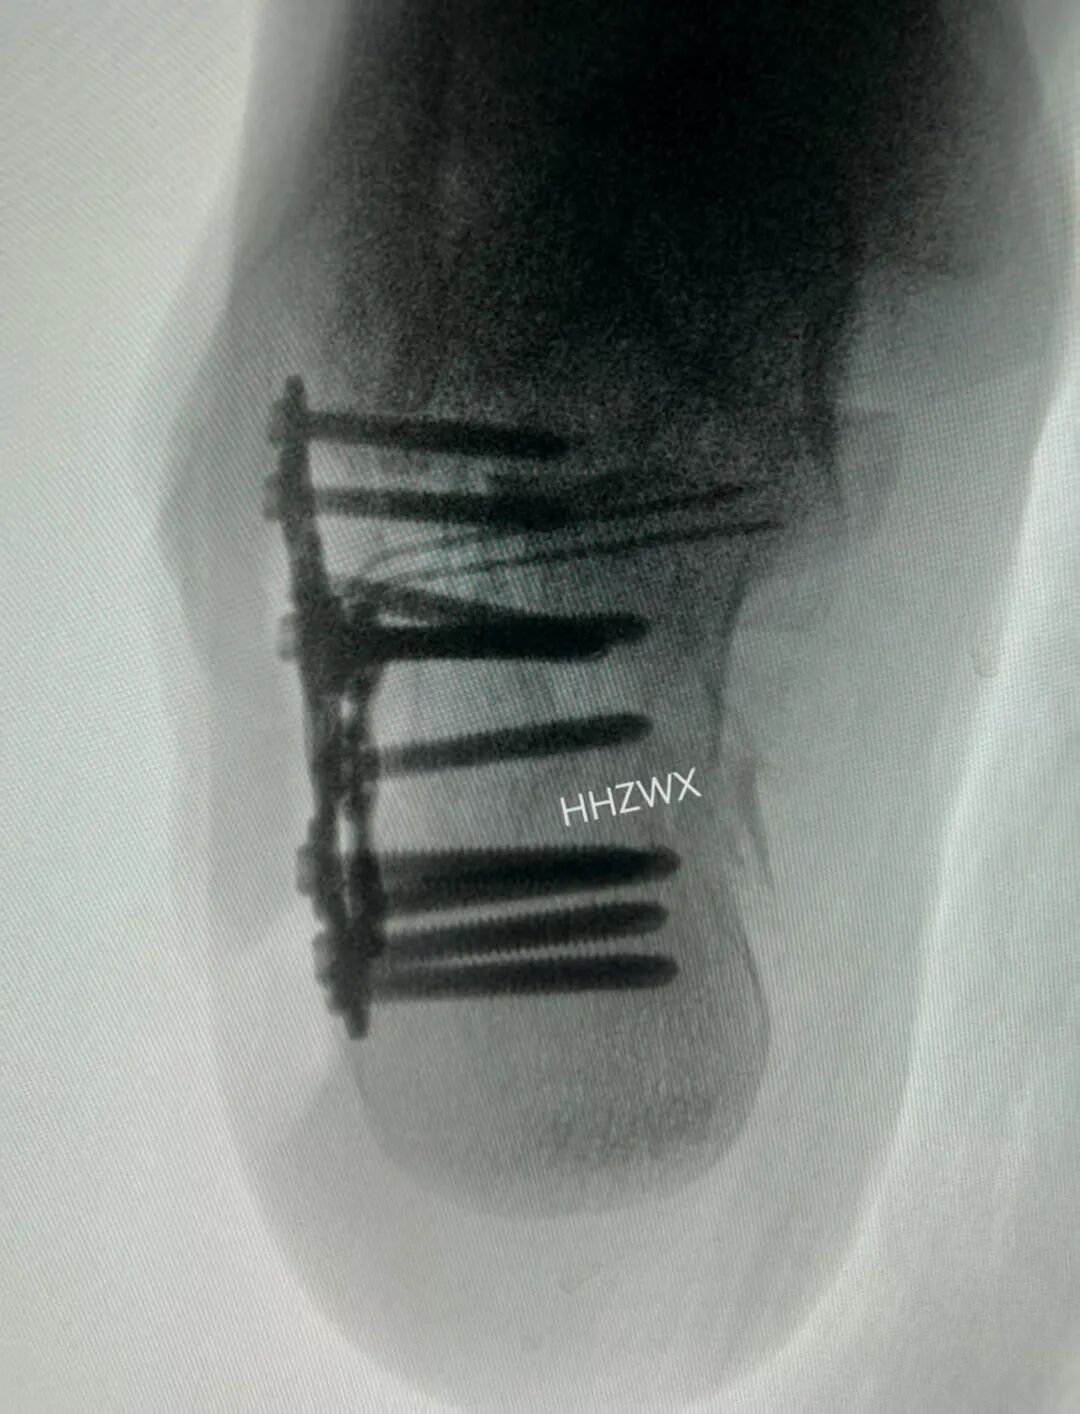

这是一例比较复杂的跟骨,合并舌型骨折块,同时内侧嵌插严重,关节面塌陷。

术中采取打开内侧壁后结合术中骨刀撑开合并上述手法复位内翻,然后给予克氏针固定与稳定的载距突,达到矫正并稳定内翻复位。(很多人复位位置很好,但总是固定不住,最主要的原因就是没有固定骨折块于稳定的骨折块上,固定于载距突可以很好的解决这个问题)

解决内翻之后,复位关节面,同时复位G角和舌型骨折块,辅助克氏针临时固定,可以很好的固定骨折。术中可以看到解剖复位。

这一例也是采用同样的方法,复位内翻之后,克氏针临时固定,钛针固定载距突方向复位关节面。最终解剖复位。